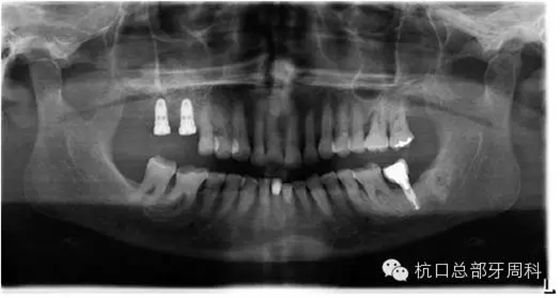

2013.1

114.webp.jpg

2013.3

下頜所有牙齒自動(dòng)脫落,炎癥累及整個(gè)下頜骨,包括左側(cè)髁狀突,病理性骨折左側(cè)聽力喪失

115.webp.jpg